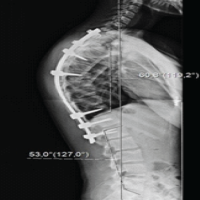

An intraneural ganglion cyst is a mucin-filled lesion within the epineurium, enclosed by a fibrous wall, that causes neuropathy through fascicular compression [9]. Several pathogenetic mechanisms have been proposed. The intraneural theory attributes cyst formation to repetitive microtrauma and subsequent mucoid degeneration of fibrous tissue [7]. However, the most widely accepted explanation is Spinner’s articular theory, in which a capsulolabral tear permits joint fluid to track along the articular branch into the nerve, with dynamic joint pressures influencing cyst size and extension [3,4,6,8]. Cross-over into adjacent nerves may occur through a shared epineural sheath [4,6]. Our case supports this mechanism: the cyst arose from a capsulolabral tear. Arthro-MRI confirmed a SLAP lesion, with joint fluid tracking along the articular branch to the suprascapular and Spinoglenoid notches, causing suprascapular neuropathy. Both supraspinatus and infraspinatus were affected, the latter more severely. Supraspinatus dysfunction likely limited overhead activity, while infraspinatus weakness reduced external rotation strength. Sensation was intact bilaterally, consistent with the SSN’s lack of a cutaneous branch [1]. Imaging showed no atrophy, but EMG demonstrated active denervation; follow-up EMG revealed improved supraspinatus recruitment and CMAP amplitude, with severe decreased recruitment and denervation in infraspinatus muscle. Three potential propagation patterns can be considered: (1) two independent primary cysts originating from the superior and inferior branches, (2) a primary cyst arising from the superior branch with distal cross-over into the infraspinatus branch, or (3) a primary cyst from the inferior branch with proximal ascent and cross-over to the supraspinatus branch (Fig. 2). Based on previously described propagation models [4,6], the third hypothesis appears most consistent – representing a primary articular connection at the spinoglenoid notch with proximal intraneural extension and cross-over within the upper trunk. It is conceivable that following needle aspiration, transient pressure changes within the cyst may have facilitated further fluid migration along this inferior pathway. Moreover, the persistent lack of reinnervation in the infraspinatus branch could indicate that the inferior branch served as a principal site of fluid influx and pressure propagation, thereby sustaining localized fascicular injury and delayed recovery. In this case, the intraneural ganglion cyst was confirmed by ultrasound (Fig. 3) and arthro-MRI (Fig. 4).

Figure 4: Dual-site compression of the suprascapular nerve. This figure illustrates the dual-site compression caused by a suprascapular intraneural ganglion cyst at the suprascapular and spinoglenoid notches. The most likely hypothesis is that a primary cyst was formed at the spinoglenoid notch due to mucinous fluid traveling along the inferior articular branch. Proximal ascent and cross-over to the supraspinatus branch subsequently led to the formation of a secondary cyst at the suprascapular notch. Br. SA: Superior articular branch, Br. IA: Inferior articular branch, Br. SS: Branch to the supraspinatus, Br. IS: Branch to the infraspinatus.